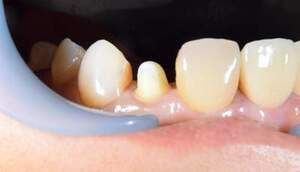

| 年齢 | 30代女性 |

|---|---|

| 主訴 | 前歯がとれた |

| 治療方針 | 右上2が残根状態になっています。歯の保存をするためには歯を挺出させるしかありません。 |

| 治療期間 | 9ヶ月(途中、3ヶ月程中断あり) |

| 費用 | ・MTM 110,000円 ・ファイバーコア 16,500円 ・セラミッククラウン 110,000円 |

※全て税込となります。

左の写真は歯が歯肉縁上にないのがわかります。右では歯肉縁上に1周にわたって歯牙があるのがわかります。

レントゲンで見ても、右上2では歯質が歯肉縁上にのこっていない。しかし歯根は長いのでMTMの適応症例です。